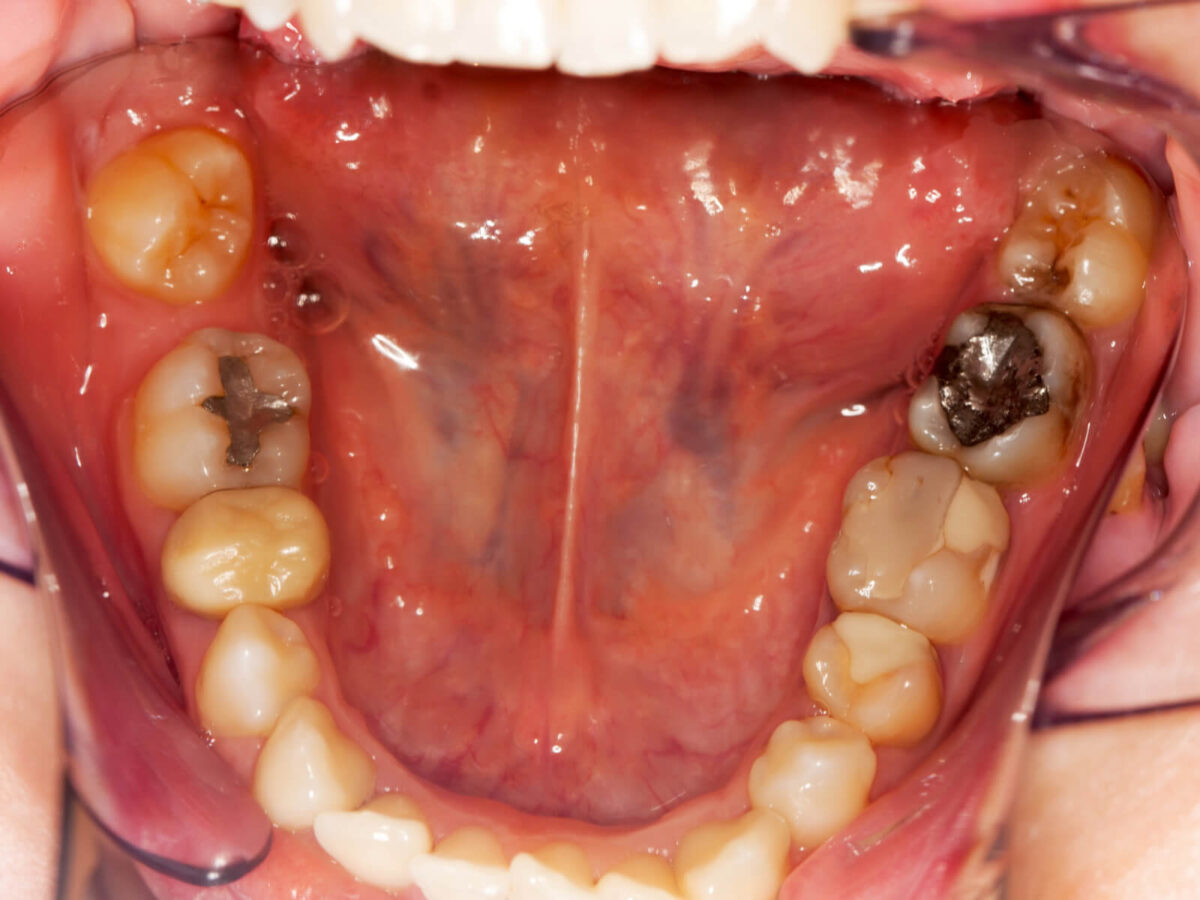

You Can See a Spot or Hole

Sometimes, the signs are visible. Look in the mirror. If you see a little dark dot or even a tiny hole in your tooth, don’t shrug it off.

That’s likely where decay has started. Even if it doesn’t hurt (yet), it’s not normal. Cavities love to hide in places like that.

A filling here is fast and painless. But if ignored? It spreads. And then you’ve got a bigger problem.

• White composite: Matches your tooth. Great for front teeth.

• Silver (amalgam): Super strong. Best for back molars.